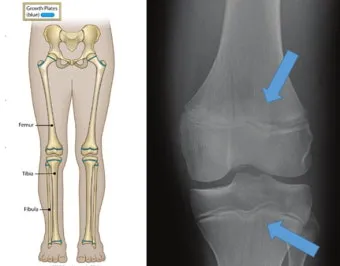

성장판은 하나의 문이 갑자기 '딱' 닫히는 것이 아닙니다. 손가락, 발가락, 손목, 발목, 골반, 척추 순으로 뼈 끝 쪽의 연골이 굳어져 가는 과정은 꽤 오랜 시간이 걸려요. 성장판의 닫히는 시기는 개인차가 매우 크답니다.

일반적으로 여성은 14-15세, 남성은 16-17세에 성장판이 닫히기 시작하지만, 완전히 닫히는 것은 만 19-20세경이에요. 하지만 여기서 중요한 건, 성장판 검사에서 '닫혔다'고 나와도 검사 오차가 있을 수 있고, 미세하게 남아있는 성장판으로 인한 성장 가능성이 남아있다는 점입니다.